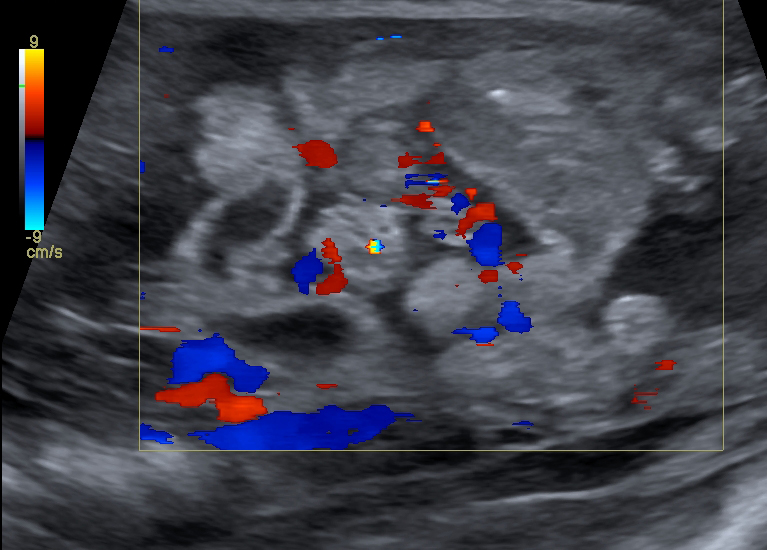

La enterocolitis necrosante (NEC) es una condición grave en neonatos, especialmente en aquellos prematuros, y la ecografía abdominal se ha convertido en una herramienta valiosa para su diagnóstico y manejo. Los hallazgos ecográficos en neonatos con NEC incluyen una serie de características que pueden ayudar a identificar la gravedad de la enfermedad y la necesidad de intervención quirúrgica.

1. Neumatosis intestinal: La presencia de gas en la pared intestinal es un hallazgo clásico y altamente sugestivo de NEC.

4. Gas portal venoso: La presencia de gas en la vena porta es otro hallazgo ecográfico que puede estar presente en NEC, aunque su asociación con la necesidad de cirugía o muerte no es tan fuerte como otros hallazgos.[2][4]